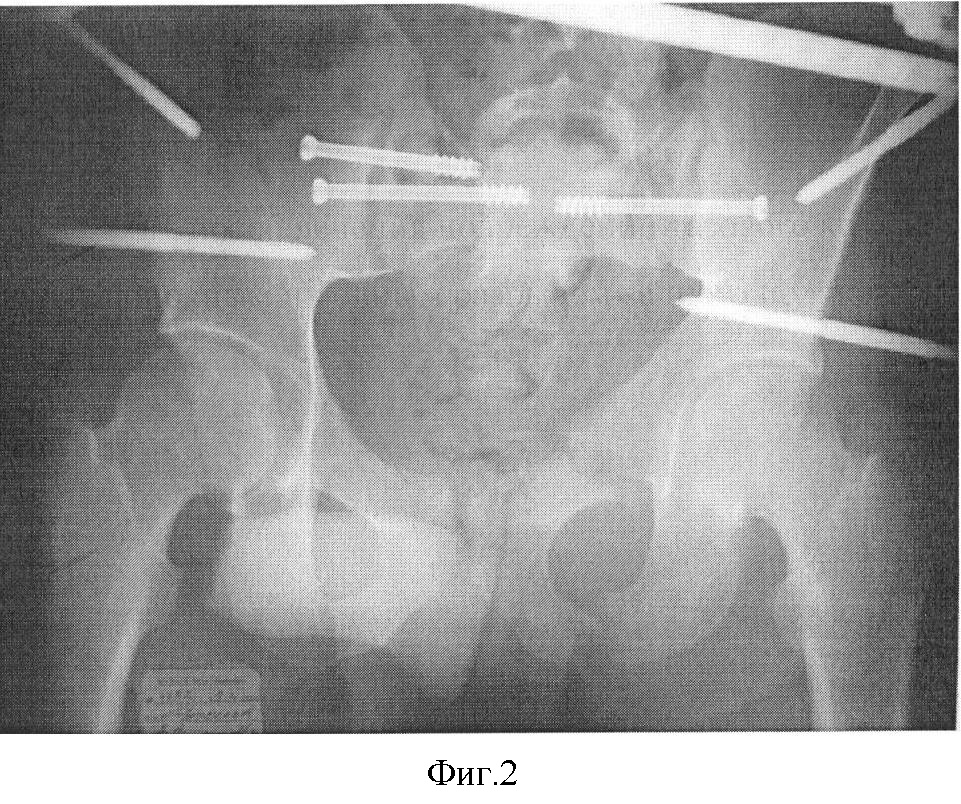

Больной находится в операционной, на рентгенпрозрачном столе, на неповрежденном боку, под спинальным или эндотрахеальным наркозом. После обработки операционного поля во многих случаях смещение сразу репонируется, если не происходит точного сближения лонных костей, и задняя верхняя ость подвздошной кости продолжает выступать, то давлением на гребешок смещенной подвздошной кости она толкается и ретируется книзу и кпереди по направлению к здоровой половине таза. Ассистент дополнительно проводит вытяжение и внутреннюю ротацию за нижнюю конечность. Далее, с помощью электронно-оптического преобразователя производят рентгенконтроль в прямой, каудальной проекциях. Если смещение устранено, то проводят по две спицы через подвздошную кость в тело крестца. Производят точечный прокол кожи, мягких тканей. По спице просверливают отверстия с помощью канюлированного сверла. Вкручивают по спицам два канюлированных винта с резьбой 32 мм, и задний комплекс жестко фиксируют. После больного переворачивают на спину с помощью ассистента, и проводят фиксацию переднего полукольца. Для этого в передневерхнюю ость крыла подвздошной кости и тело подвздошной кости (1,5-2 см выше вертлужной впадины в наиболее плотную, утолщенную часть таза) через проколы кожи, мягких тканей, с помощью троакара просверливают первый кортикальный слой и вкручивают метафизарные самонарезные резьбовые стержни, проходящие через два кортикальных слоя (фиг.2). Это позволяет уменьшить риск повреждения брюшной и тазовой полостей и более прочно стабилизировать стержни в костях. В крыльях стержни проходят в межкортикальной щели и также выходят на 1-2 мм через второй кортикальный слой. Стержни, расположенные во взаимно перпендикулярных плоскостях, соединяют с помощью балок-пластин. Введение опор в виде самонарезных метафизарных резьбовых стержней создает наиболее прочную конструкцию. Стабильная фиксация уменьшает риск возникновения нагноения мягких тканей, позволяет увеличить срок фиксации таза. Отмеченные зоны, направления и методы ввода стержней являются безопасными в плане повреждения сосудисто-нервных пучков, тазобедренных суставов, тазовых костей, перфорации брюшной и тазовой полостей.